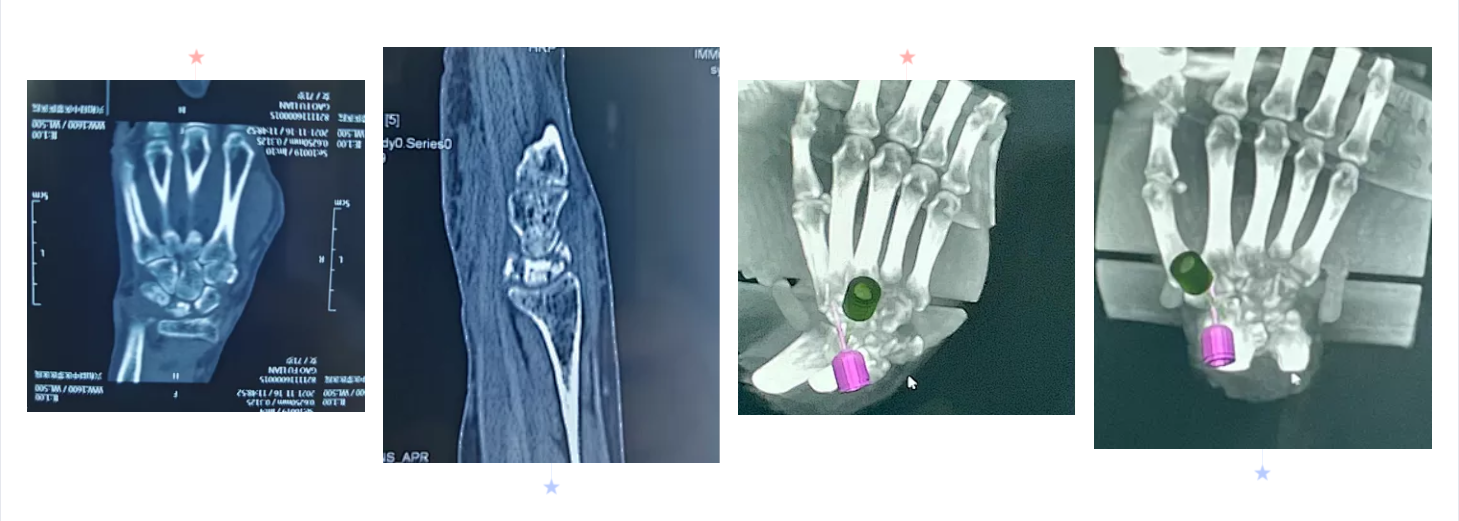

手足显微外科B区郝增涛教授团队成功完成自治区首例“天玑”Ⅱ骨科手术机器人辅助下经皮空心螺钉大小多角骨、舟骨融合术(STT融合)治疗IIIb期月骨无菌性坏死手术。手术十分顺利,固定效果满意,患者恢复良好。这是91直播

完成的首例也是自治区首例“天玑”Ⅱ骨科机器人辅助腕关节疾患手术,标志着91直播

腕部骨病、骨折的智能、精准、微创治疗达到了一个新的高度。

手腕部骨折、骨病目前是手外科领域新的热点和难点,腕骨的不规则性和关节的复杂性决定了手术难度高。常规的手术方式难以做到精准定位,术中经过C臂环扫后得到患者腕关节三维图像信息,经计算机模拟设计出最佳置钉方案,由机械臂精准引导植入各螺钉。真正做到了精准、微创治疗。